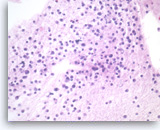

Pancreatic endocrine neoplasm #1,

Pancreas FNA, Direct Smear.

The aspirates show single and dyshesive clusters of neoplastic cells. The neoplastic cells show mild variation in size and have eccentrically located oval nuclei (plasmacytoid appearance). A few small cytoplasmic vacuoles are seen.

40X

Pancreatic endocrine neoplasm #1,

Pancreas FNA, Direct Smear.

The aspirates show single and dyshesive clusters of neoplastic cells. The neoplastic cells show mild variation in size and have eccentrically located oval nuclei (plasmacytoid appearance). A few small cytoplasmic vacuoles are seen.

40X

Pancreatic endocrine neoplasm #1,

Pancreas FNA, Direct Smear.

Dispersed dyshesive neoplastic cells have speckled (“salt and pepper”) chromatin and inconspicuous nucleoli.

40X